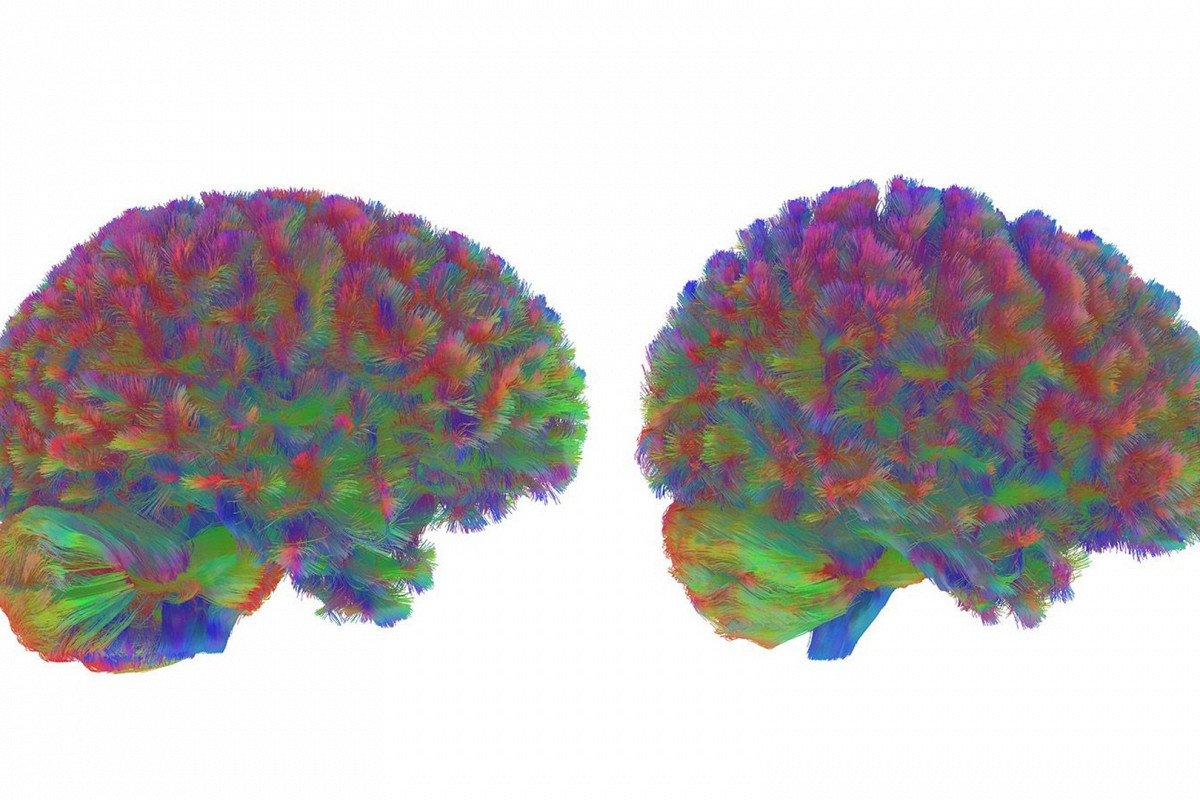

Команда ученых проанализировала мозг 3802 людей в возрасте от рождения до 90 лет при помощи диффузионной магнитно-резонансной томографии (МРТ). Этот метод позволяет отобразить нейронные связи, отслеживая движение молекул воды в тканях мозга.

Выяснилось, что мозг в течение жизни проходит пять основных стадий, разделенных «точками поворота», во время которых нейронная структура переконфигурируется.